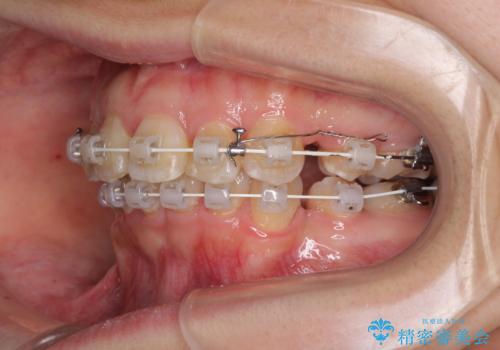

- 矯正装置

- 審美装置

- 口元の閉じにくさと、前歯のでこぼこの歯並びを気にして来院された患者様です。

口元を積極的に引っ込めるために、上下左右の小臼歯計4本を抜歯することとしました。

咬み合わせが深く、咬合力強いため、補助装置を使用しながら積極的に口元を下げることとしました。